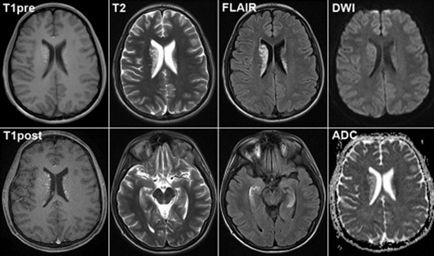

MRI се характеризира със своите предимства. Тази процедура дава възможност да се запознаят с частите на мозъка, в няколко прогнози.

Body тъкан може да се види във фронталния, сагитална, а също и в аксиална равнина. Нещо повече, то ще се окаже по-висок контраст, което не е случаят с компютърна томография.

Изображение с ядрено-магнитен резонанс няма да има никакви поправки от контакт с костта. Получената Картината показва детайл на тумора на централната нервна система или унищожаване на невронни мембрани.